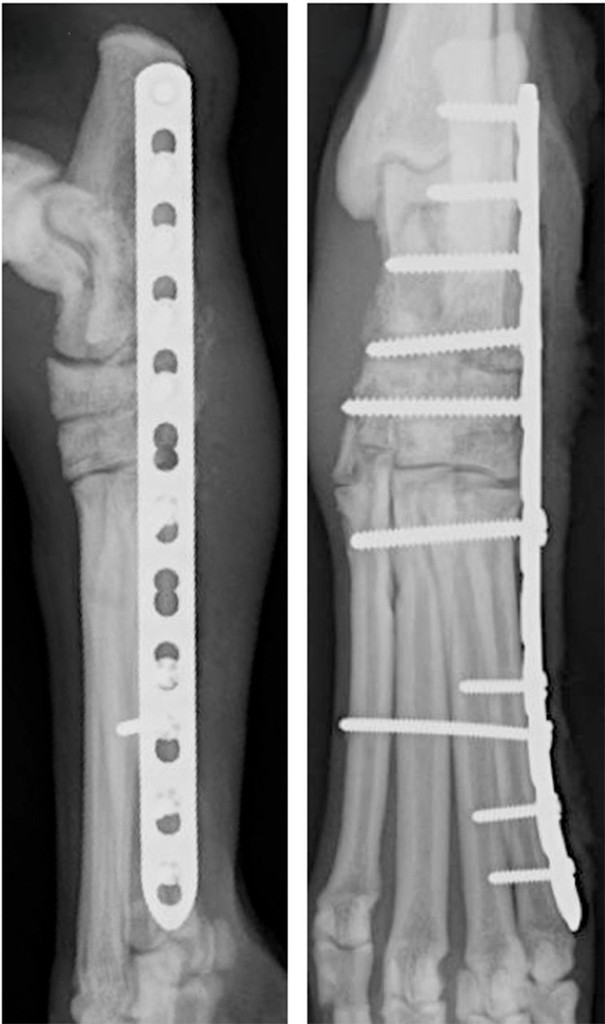

Pancarpal (Wrist)

Arthrodesis

Pancarpal/Pantarsal Arthrodesis

A complete arthrodesis involves fusion of the entire joint, eliminating all range of motion. A complete arthrodesis is necessary when the tibiotarsal or radiocarpal joints are affected. The cartilage is removed between all joints within the wrist or ankle then filled with bone graft. A specialized bone plate and screws are used to stabilize the bones until they fuse completely.

Pancarpal

(Wrist) Arthrodesis

Partial Carpal